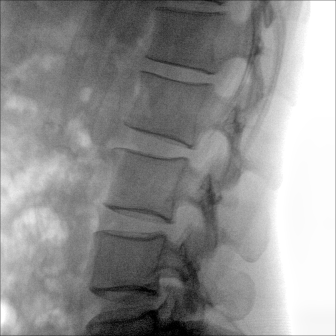

临床适用科室:骨科、普通外科、矫形外科、创伤外科、泌尿外科、脊柱外科、疼痛外科、消化科、妇科等科室。

图形化操控界面设计:设有多种人体特征摄影参数,操作简便。双向红光十字定位系统:实现无射线下的高效定位。信息共享:遵循DICOM3.0格式接口,可无缝对接云PACS系统。

多角度自由旋转,满足患者复杂摆位需求。